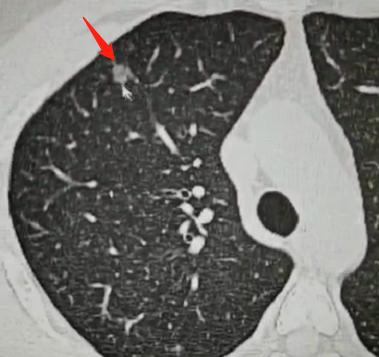

但临床中还有一种复杂情况,就是结节表现模棱两可,看着像良性,又有恶性的特征,就像擅长伪装的特务,表面和好人无异,实则暗藏风险。这种时候如果继续观察,可能会延误病情、影响健康,就不能再等,需要通过活检明确诊断。

目前常用的活检方式主要有两种:一种是气管镜,从鼻腔伸入器械进行检查;另一种是 CT 定位下的经皮穿刺。

不过这两种方式都有局限:穿刺有一定副作用,患者可能担心疼痛、气胸,或是穿刺不准;而传统气管镜就像筷子一样粗,在肺部能到达的位置有限,只能活检中央型结节,对肺外周的结节无能为力。

为了解决这些问题,我们现在有了更先进的技术 —— 超细气管镜结合机器人导航。它就像给气管镜装上了 “导航系统”,能精准指引器械左转、右转、前进、后退,让纤细的气管镜深入到肺部极远的外周位置,完成活检操作。